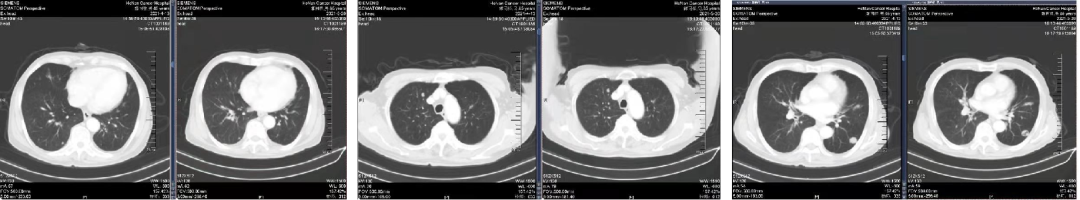

诊断:直肠腺癌双肺转移IV期,KRAS 突变型,MSS。高龄,患者及家属无手术意愿,全身系统治疗。

于2021.04.14 始行“曲氟尿苷替匹嘧啶片(TAS-102)+贝伐珠单抗”2周方案治疗至今。

04 疗效评估

患者疾病控制良好,耐受情况好。